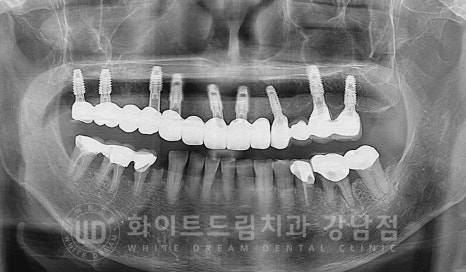

환자분의 당일 수술 후 x-ray 사진입니다.

상악 전체 임플란트 식립 후 / 수술 일자 : 23.08.10

식립된 임플란트를 보면 임플란트의 길이가 제각각인 것처럼 보이실 수 있습니다.

어떤 임플란트는 1차 수술만 진행하고, 어떤 임플란트는 2차 수술까지

진행했기 때문인데요.

자세히 보겠습니다.

초기 염증이 심했던 부위에 식립된 임플란트는 1차 수술만 진행했고

골질이 양호한 부위의 임플란트는 2차 수술까지 진행한 상태입니다.

왜 이렇게 다르게 수술을 진행하는 것일까요?

그 이유는 임플란트 식립 후 안정적인 고정력이 나오지 않기 때문입니다.

임플란트 식립 후 확인되는 초기 고정력은 기존에 있던 뼈로 인해 나오게 되고

최종 임플란트 보철 체결 전 확인하는 고정력은 식립된 임플란트 주위 형성되는

새로운 뼈로 인해 발생합니다.

기존 식립 부위에 임플란트가 안정적으로 초기 고정력을 발휘할 만큼의 잇몸뼈가 있을 때

1차, 2차 수술을 동시 진행합니다.

하지만 잇몸뼈가 염증으로 녹아 부족한 상태이거나

골질이 좋지 못하면 초기 식립한 임플란트가 불안정한 상태이기에

잇몸뼈 안에 매복해둔 상태로 자리 잡을 수 있도록 1차 수술만 진행하는 것이죠.